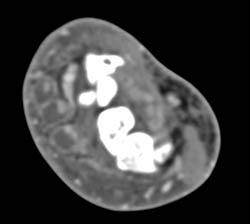

Lisfranc Fracture and Dislocation